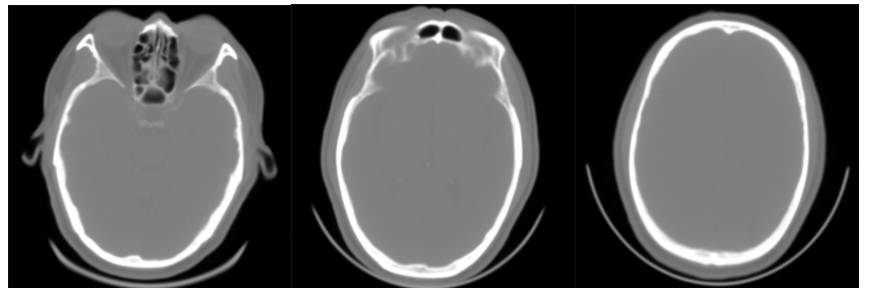

16层CT头部扫描(正常志愿者)

16层移动CT脑部扫描

16层移动CT脑部扫描(骨窗像)